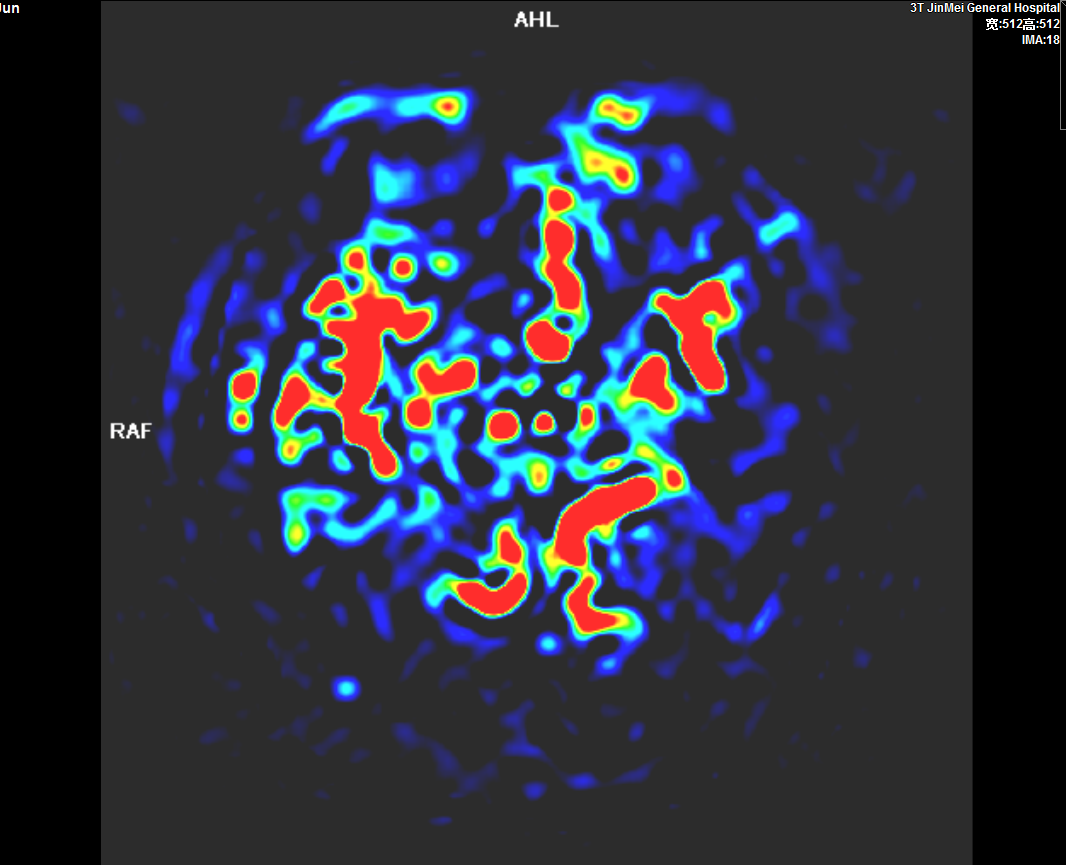

頭顱灌注成像ASL

3、MRI的功能成像評(píng)價(jià)超急性期腦梗死,指導(dǎo)臨床治療;CTP、PWI成像評(píng)價(jià)腦缺血性病變、腫瘤性病變;CTA、MRA評(píng)價(jià)顱內(nèi)外血管性病變。